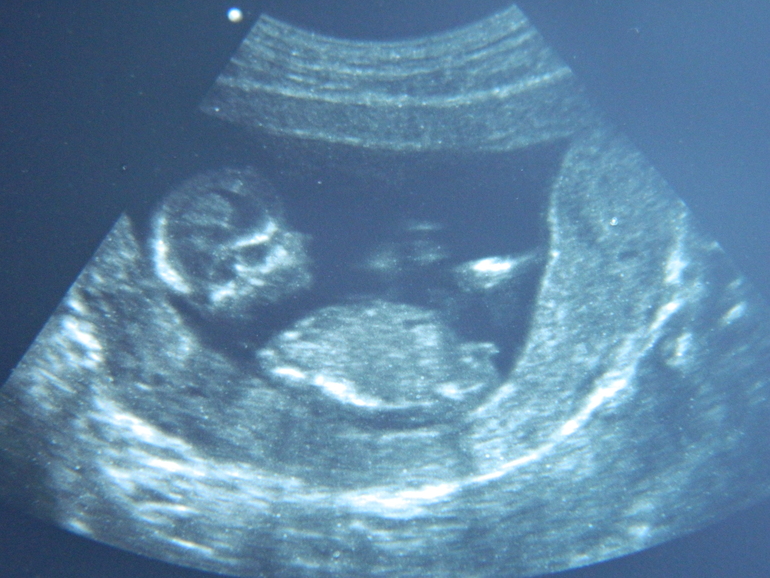

Сходили на узи,12,5 недель по М.Ктр - 68мм соответствует 13.1недель.Чуть опережаем)Все у нас хорошо.Твп и носик в норме.

Зорким глазом гляньте , скажите,хоть кому-то мальчик видется??

Девочка. Бугорок параллельно спинке. Именно в этом ракурсе как раз смотрят в 12 нед:)